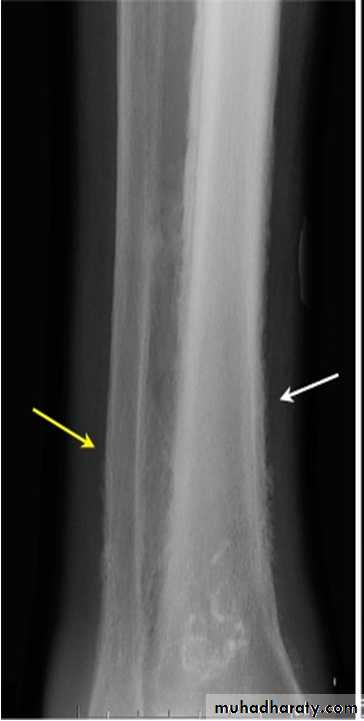

squamous cell carcinoma in which a portion of the tumor demonstrates central cavitation,

Hypertrophic pulmonary osteoarthropathy (HPOA). This is a painful periostitis of the distal tibia, fibula, radius and ulna, with local tenderness. X-rays reveal subperiosteal new bone formation. While most frequently associated with bronchial carcinoma, HPOA can occur with other tumours.